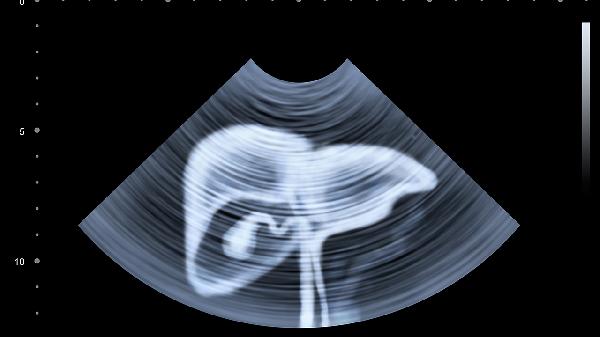

56岁女子腹痛腹胀,医生手心冒汗,赶紧做个CT,医生:肝癌晚期

那位女士的CT结果出来后,肝区已经布满"雪花状"的肿瘤。其实三个月前她体检时肝功能只有轻微异常,要是当时做个增强CT...健康从来不会和你开玩笑,它只会用最残酷的方式提醒你:有些检查,真的等不起。